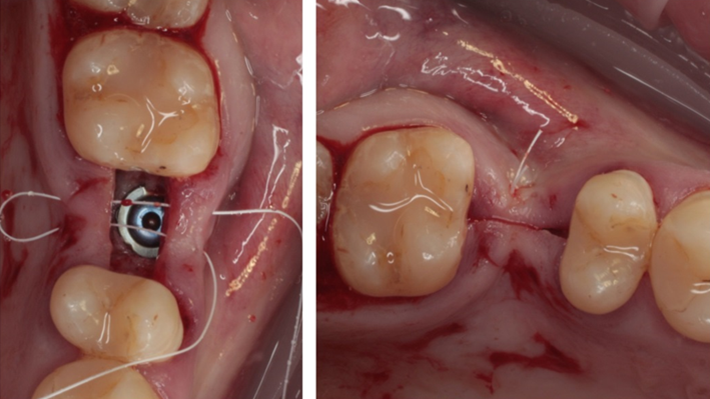

Clinical case: # 46 implant placement & GBR using i-Gen membrane for significant vertical resorption & mixed bone defect

- Courtesy of Dr. Iulian Filipov, Romania -

AnyRidge, mandibular posterior, i-Gen, resorption, bone defect, bone regeneration, space management, #46, GBR, Dr. Iulian Filipov

AnyRidge implant system, i-Gen